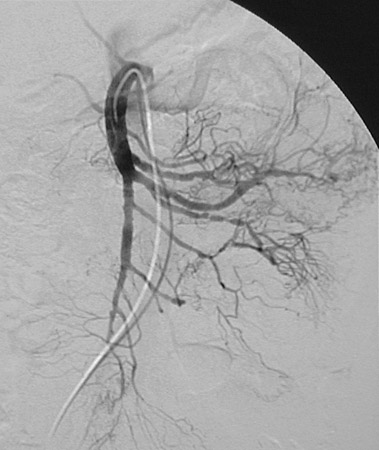

In this angiogram of the superior mesenteric artery can be seen arterial wall irregularity along with distal microaneurysm formation in vessels with abrupt termination. This is a case of polyarteritis nodosa.